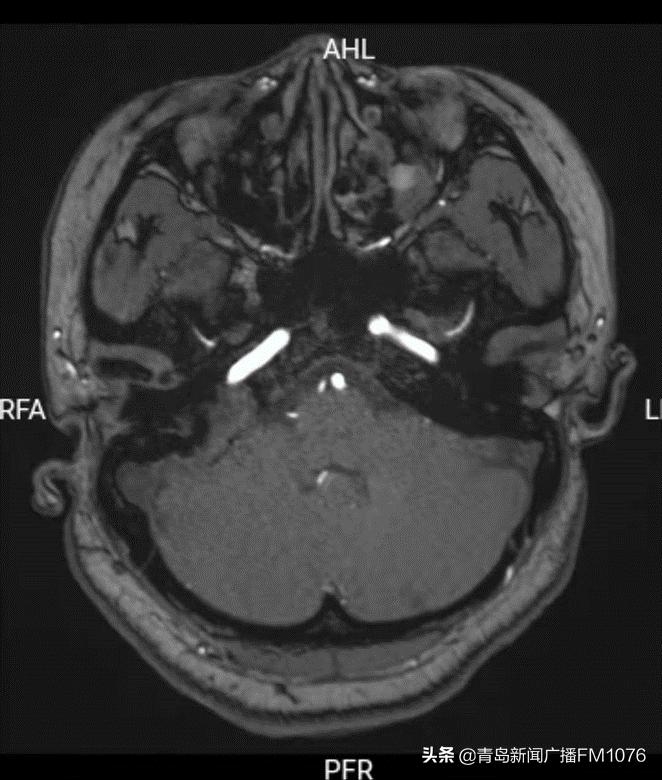

患者的病变位于右侧颈静脉孔区-颞骨岩尖部-后颅窝部,有一块很大的不规则软策划影,周围骨质已经出现破坏,病变周围密布着颈内动脉、乙状窦、颈内静脉、面神经。李主任非常清楚,这是一颗十分“狡猾”的肿瘤,不仅位置深在,而且它周围布满神经血管,稍有不慎,便会给患者导致更大的伤害。患者已出现面部抽搐,表明肿瘤已经刺激到面神经,如不尽快手术,肿瘤会不断增长,患者将会出现面瘫、颅内感染等更严重症状。

肿瘤周围相关的神经血管结构示意图

入院后,进一步完善了包括面神经肌电图、听力学、颞骨中耳乳突薄层平扫、颞骨3D模型打印等个性化检查,充分掌握了肿瘤的形态及与周围策划的毗邻关系,团队经过讨论,决定采用经耳囊入路手术。选择该入路最大的原因是能够保留面神经行程位置不动,在面神经前下面和后面磨除周围骨质到达病变部位,可以保留面神经功能,但同时也对术者提出了很大的挑战性:该入路存在局部暴露不充分的缺点,大大增加了手术难度。“一个正确的手术入路,是手术成功的关键,虽然经耳蜗进路暴露更好,但需要面神经移位,术后面神经功能有影响,我们要尽最大努力保全患者神经功能,而且团队有信心通过精湛的内镜技术弥补手术暴露的缺陷。”李永团主任表